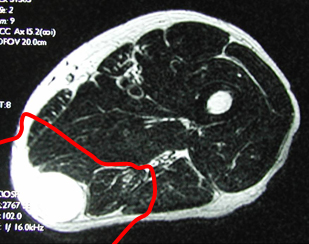

骨表面の膜(骨膜)、軟骨、筋表面の膜(筋膜)などを腫瘍の浸潤を防ぐ組織(バリアー)と見なし、このバリアーで腫瘍を包むように切除する手術です(治癒的切除)。バリアーの無い部位では腫瘍からできるだけ離し正常組織(腫瘍辺縁からの距離を計算;○cm)を含めて切除します(○cm広範切除)。安全な切除縁で腫瘍を切除することが重要であり、術後再発率はほぼ5%程度になります。当科では、MRIやCT像を基にバリアーの存在を診断し綿密に手術計画を立て、3cm以上の広範切除獲得を基本としています。